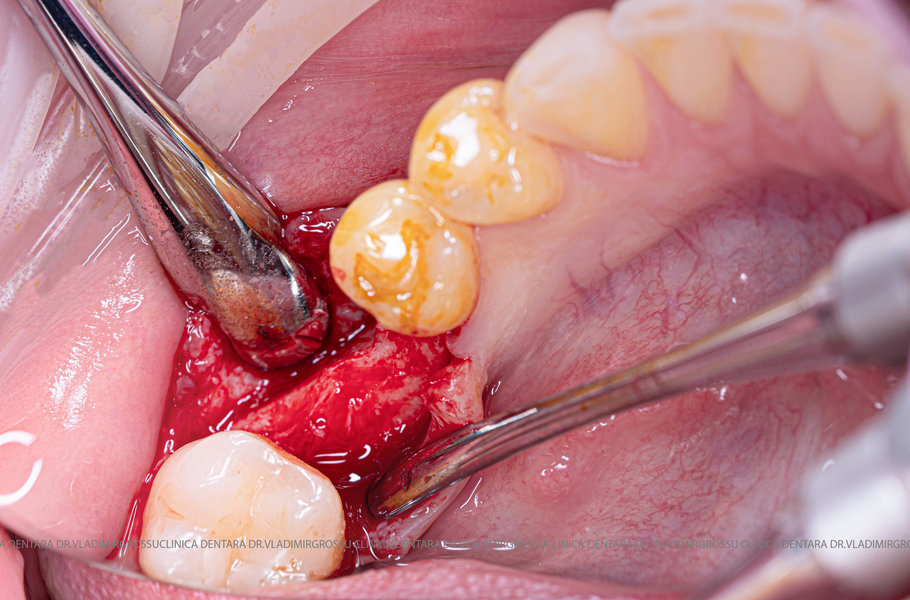

După extracția dentară, în intervalul de 6-12 luni, osul alveolar suferă un proces natural de remodelare, ceea ce conduce la scăderea volumului osos prin rezorbție. De aceea, inserția implantului dentar este ideală imediat după extracție sau, cel târziu, în primele 3-4 luni după aceasta.Scopul procedurilor de adiție osoasă este refacerea fundației osoase necesare pentru stabilizarea corectă a implantului dentar. Pentru ca un implant să reziste în timp la forțele masticatorii, este nevoie de o bază osoasă solidă și sănătoasă.

Un element esențial în procedura de aditie osoasă este utilizarea membranelor biologice, care izolează materialul osos de țesuturile moi (gingie) pe durata procesului de vindecare. Cele mai recomandate sunt membranele resorbabile din colagen sau pericard.